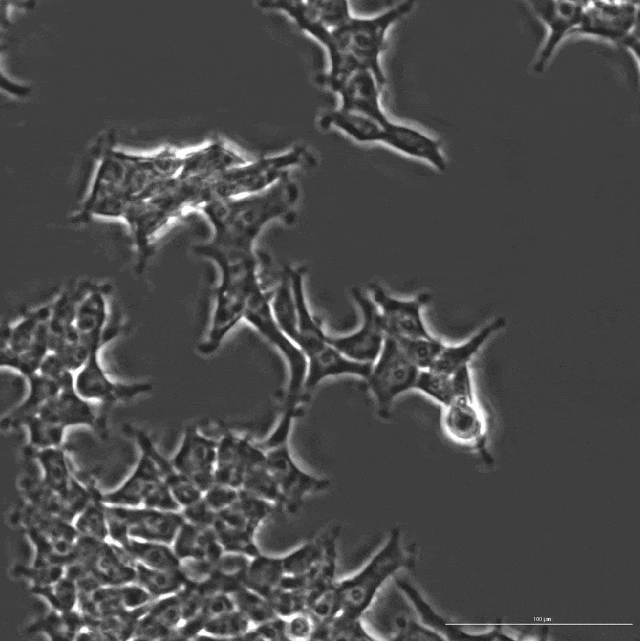

OpenCRISPR-1的物理结构,OpenCRISPR-1即是由Profluent的AI技术创建的基因编辑器Profluent联创Ali Madani表示,「尝试用AI设计的生物系统,编辑人类DNA是一次科学登月之旅」。「我们的成功表明,在未来,AI可精准设计出一系列定制的疾病治疗方案」。有网友表示,「是时候重新编程人类了吗?AI驱动的CRISPR技术进步,正挑战着基因伦理的边界」。

基因编辑器OpenCRISPR-1,由一个Cas9样蛋白质,和引导RNA(guide RNA)构成。正如之前所述,它是完全由Profluent的AI大模型开发的。在具体实现过程中,研究人员对26TB组装的「基因组」和「元基因组」数据库系统进行挖掘,整理出超100万个CRISPR操纵子(operon)的数据集。通过训练OpenCRISPR,AI从大规模序列和生物背景中学习,生成了自然界不存在的数百万种CRISPR样蛋白。研究人员称,AI生成了自然界中已发现的「CRISPR-Cas家族」的4.8倍的蛋白质集群,完全实现了指数级扩展!而且,语言模型还为类Cas9效应蛋白定制了单引导RNA序列。与原型基因编辑效应器SpCas9相比,几个生成的基因编辑器显示出,可比或改进的活性和特异性,同时在序列上相差400个突变。最后,研究人员还证明了AI生成的基因编辑OpenCRISPR-1与碱基编辑的兼容性。AI生成4.8倍「CRISPR-Cas」蛋白质宇宙